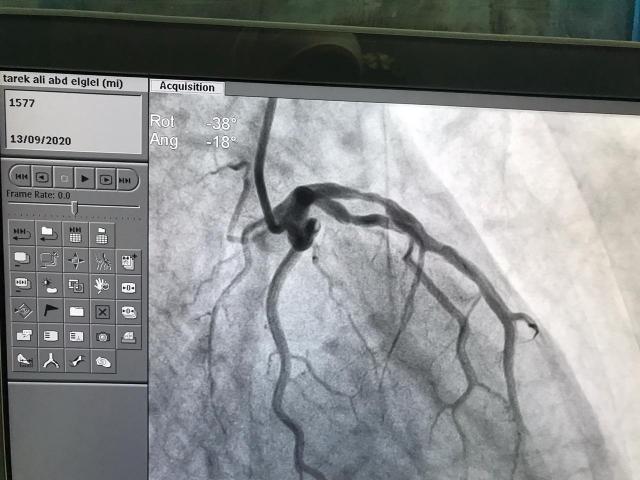

أعلن اليوم الدكتور سعد مكى وكيل وزارة الصحة بالدقهلية عن قيام فريق طبى بمستشفى المنصورة العام الجديد (الدولي) ،بانقاذ حياة مريض يبلغ من العمر 57 عاما كان يعاني من آلام شديدة وهبوط بعضلة القلب وعرق غزير ، حيث تمكن الفريق الطبي من استقبال المريض وعمل تشخيص مبدئي برسم القلب بالطوارئ و تبين وجود ذبحه شديده وجلطه بالشريان التاجى و تم دخول المريض على الفور العنايه الفائقه للقلب وإعطاء مذيب الجلطات حيث تلاحظ تدهور حالة المريض الامر الذي استلزم من إدارة المستشفى التدخل السريع لانقاذ المريض وعلى الفور تم استدعاء فريق القسطرة للتدخل حيث تمت موافقة ادارة المستشفى على عمل قسطرة تشخصية وعلاجية عاجلة كما تم تركيب دعامة بالشريان الأيسر دون انتظار قرار نفقة الدولة وذلك لانقاذ المريض،.